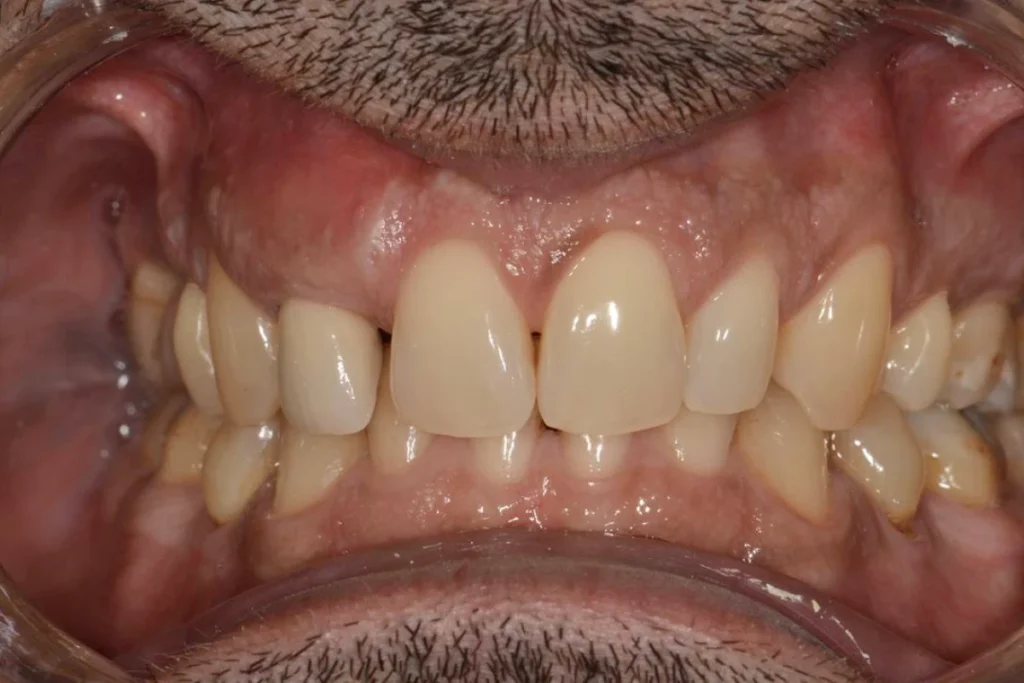

L’intervention est réalisée sous anesthésie locale et doit être complètement indolore. Le patient est revu 3 mois après l’intervention pour prendre une empreinte. Le patient est invité à se rendre au laboratoire de prothèse situé dans le 17ème afin de discuter de la forme de la dent avec l’artisan céramiste. Dans le cas présent, il souhaitait conserver l’écart existant entre ces incisives afin de conserver l’identité de son sourire.

Lors de cet entretien, le prothésiste enregistre également toutes les données de teinte et d’état de surface des dents adjacentes afin de faire la parfaite illusion d’une dent naturelle.

Environ une semaine après la prise de l’empreinte, un essayage est réalisé au cabinet. Si tous les paramètres esthétiques et fonctionnels sont validés, la couronne est posée dans la foulée.

Il est parfois nécessaire de prendre le temps d’une retouche au laboratoire afin d’obtenir le rendu escompté.